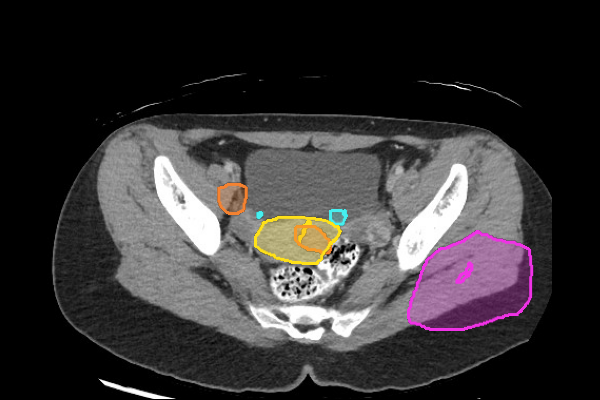

Legend

- Kidney masses are also overlooked. Look carefully at the collecting system and for renal contour abnormalities.

- Even without hydronephrosis, consider the possibility of ureteral calculi and attempt to follow the course of the ureters to screen for stones.

- Look carefully for small stones in the ureter/UVJ. Familiarize yourself with the normal location of the ureterovesical junctions and the configuration of the distal ureter to discriminate phleboliths from potential distal ureteral calculi